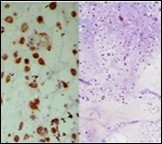

Figure 1.Parachordoma on fine needle aspiration cytology depicting clusters of spheroidal cells with eosinophilic cytoplasm, regular nuclei and clumped, encompassing myxoid stroma 13.

Figure 2.Parachordoma delineating clusters of vacuolated, spherical cells with acidophilic cytoplasm, uniform nuclei and an immune non reactive CD34- 13.